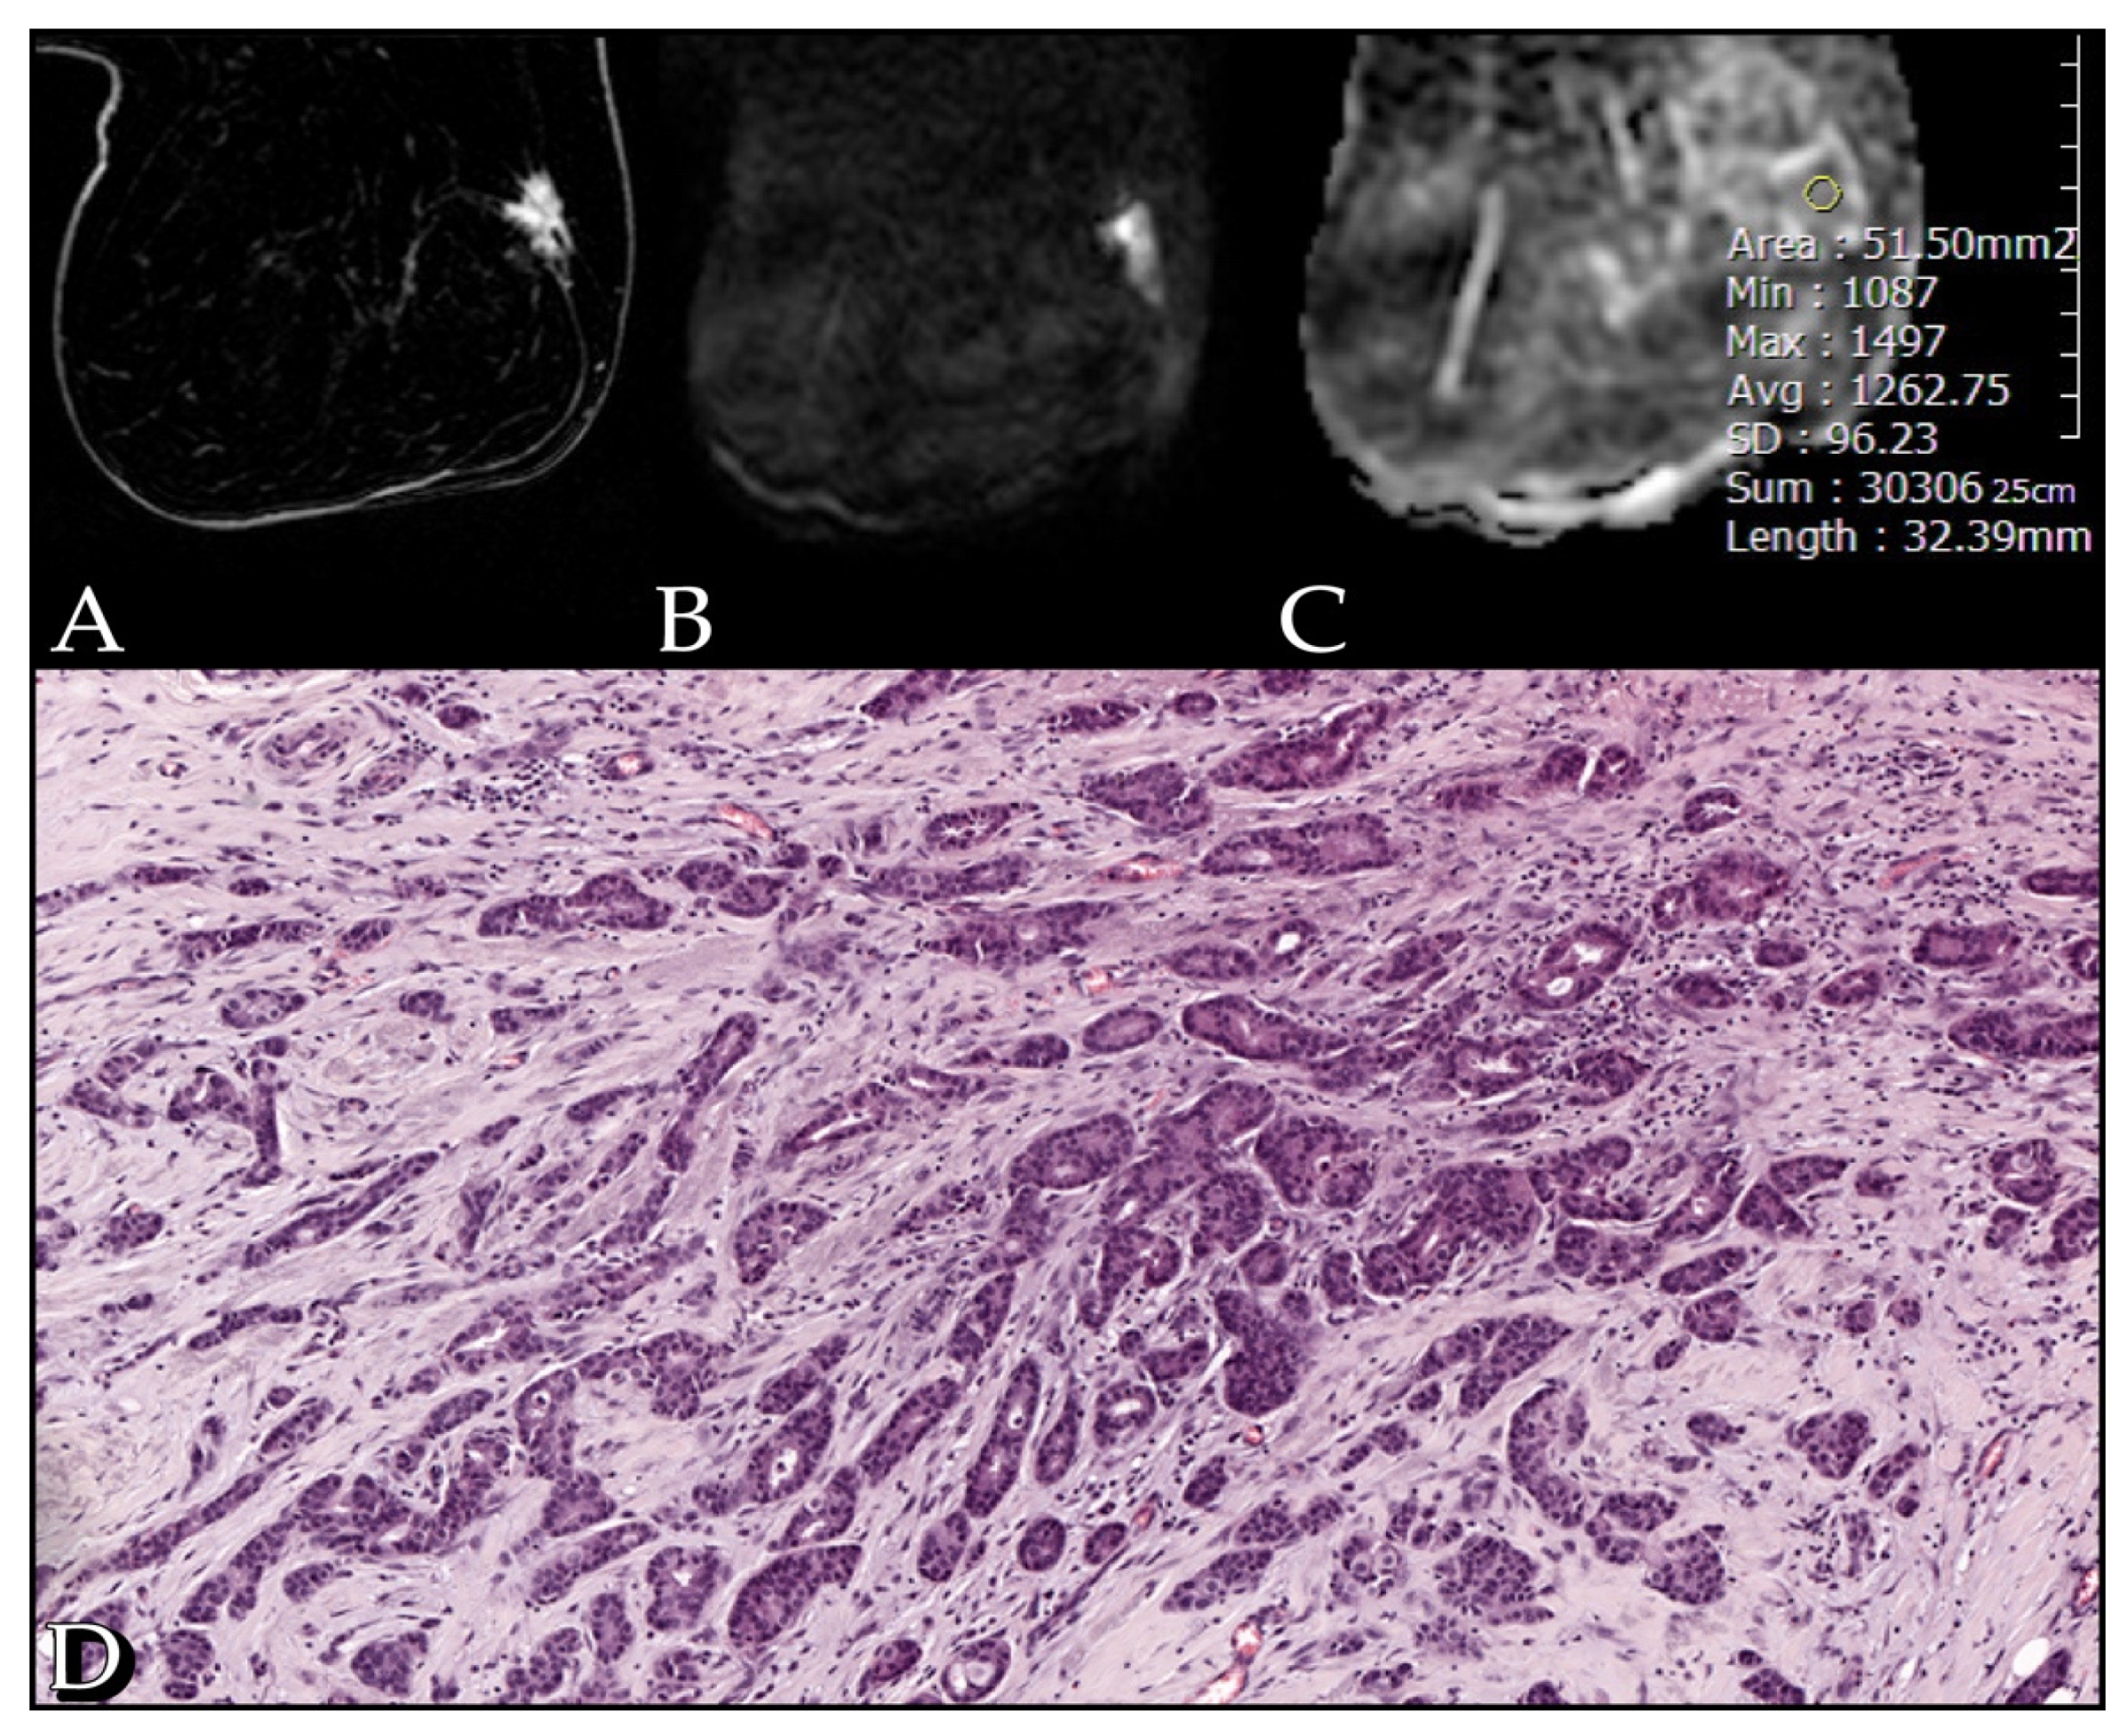

3. Results